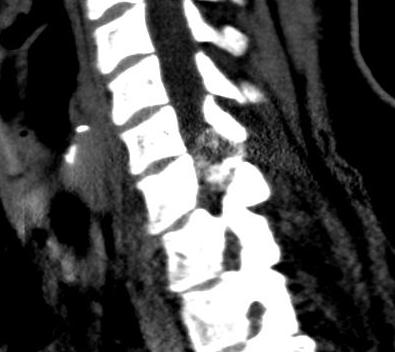

Spine

- difficult to see

- irregular cortex

- sclerotic or loss of pedicle

- enlargement of spinous process

CT

Lucent lesion with nidus or calcification

Spinal lesion

- bone expansion

- intralesional stippled ossification